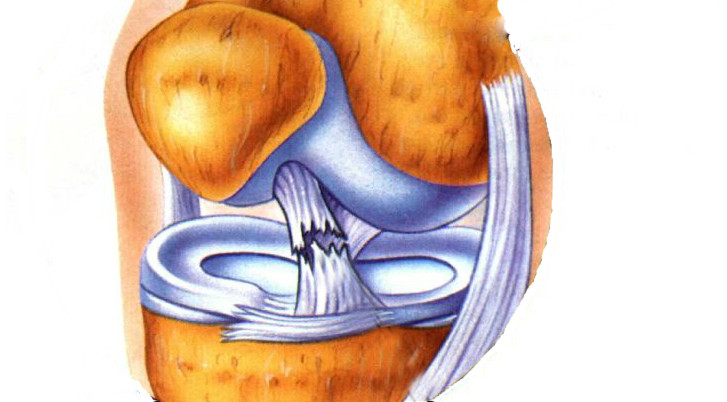

I played soccer year around. It went like this till middle school. When middle school I played starting varsity all three years. I played travel during off season. then my freshman year of high school came and during preseason I got hurt we thought everything was ok so I stop for a few games. I went back and played all JV and half of V when a girl took me out. it turned out when I got hurt bi tore my acl, menuscuse. and damaged the outside legaments. I was out for the rest of school and travel. From there is were I am at now.